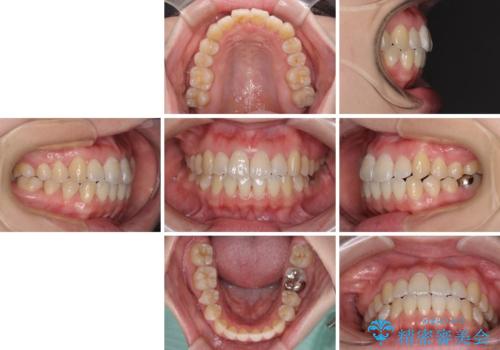

口元の突出感を改善 インビザラインによる非抜歯矯正

インビザラインでの歯列全体の後方移動は時間がかかりますが、しっかりと装着時間を守っていただいたので、スッキリとした口元に仕上げることができました。